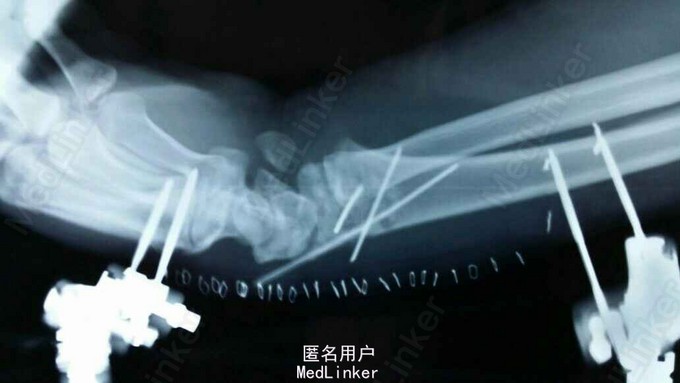

患者于2015年8月18日从高处坠落(约7米)伤及双碗,肿胀,畸形,活动受限。

双碗畸形明显,肿胀明显,可见明显皮下淤血,压痛阳性,可触及明显骨察感及骨察感,左手有明显正中神经压迫症状。

诊断:双尺桡骨远端粉碎性骨折 治疗:入院后,给予手法复位夹板固定,左手神经症状明显缓解,给予对症治疗,消肿后,于2015年8月27日行手术治疗。

请问大家,对于这种骨折是行外架+克氏针固定好,还是钢板固定好?